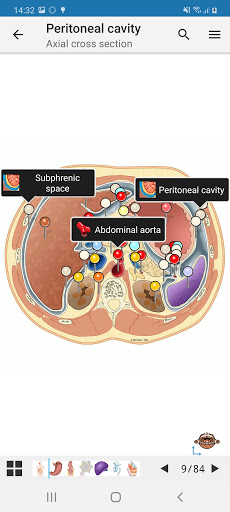

* وحدة جديدة للمستخدمين المتميزين: تشريح البطن والحوض لدى الأنثى على التصوير المقطعي المحوسب